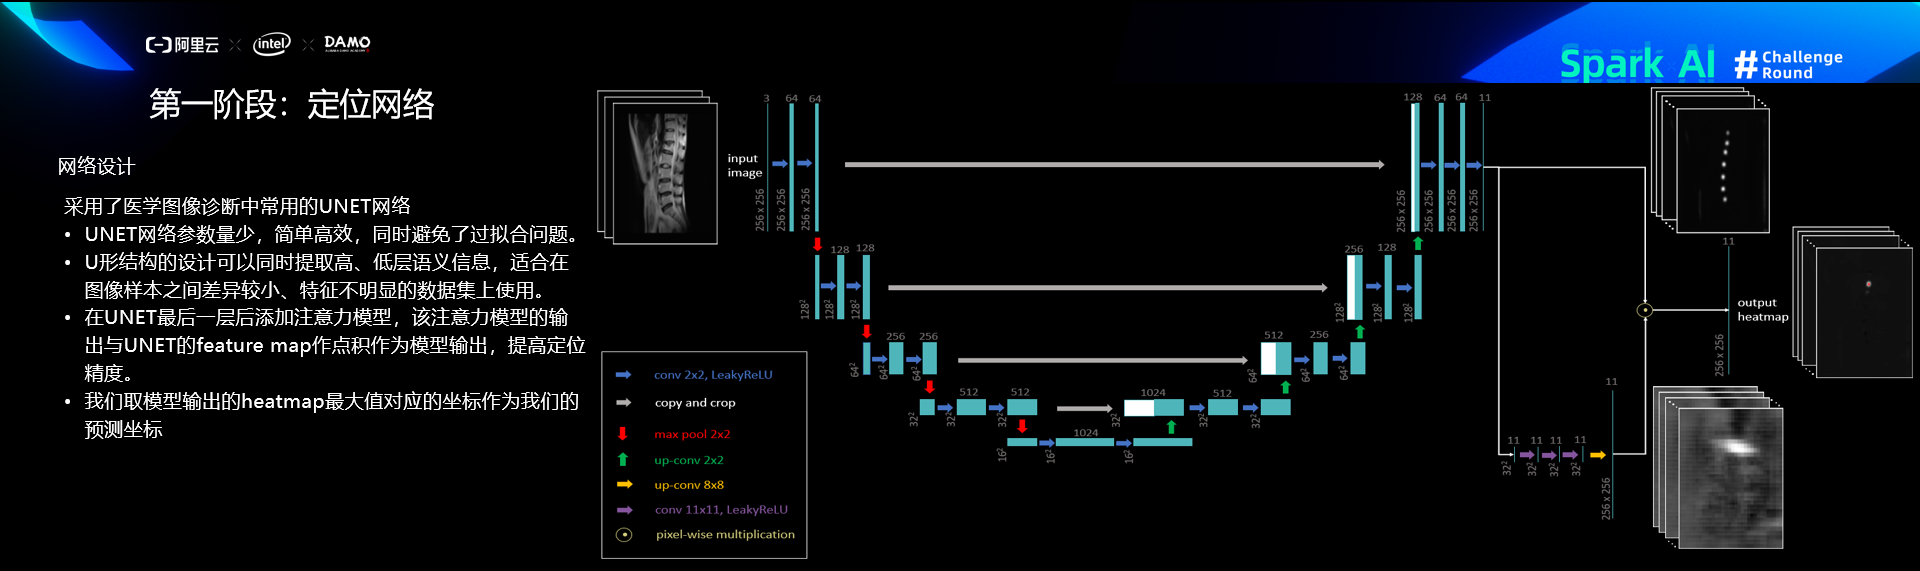

定位网络